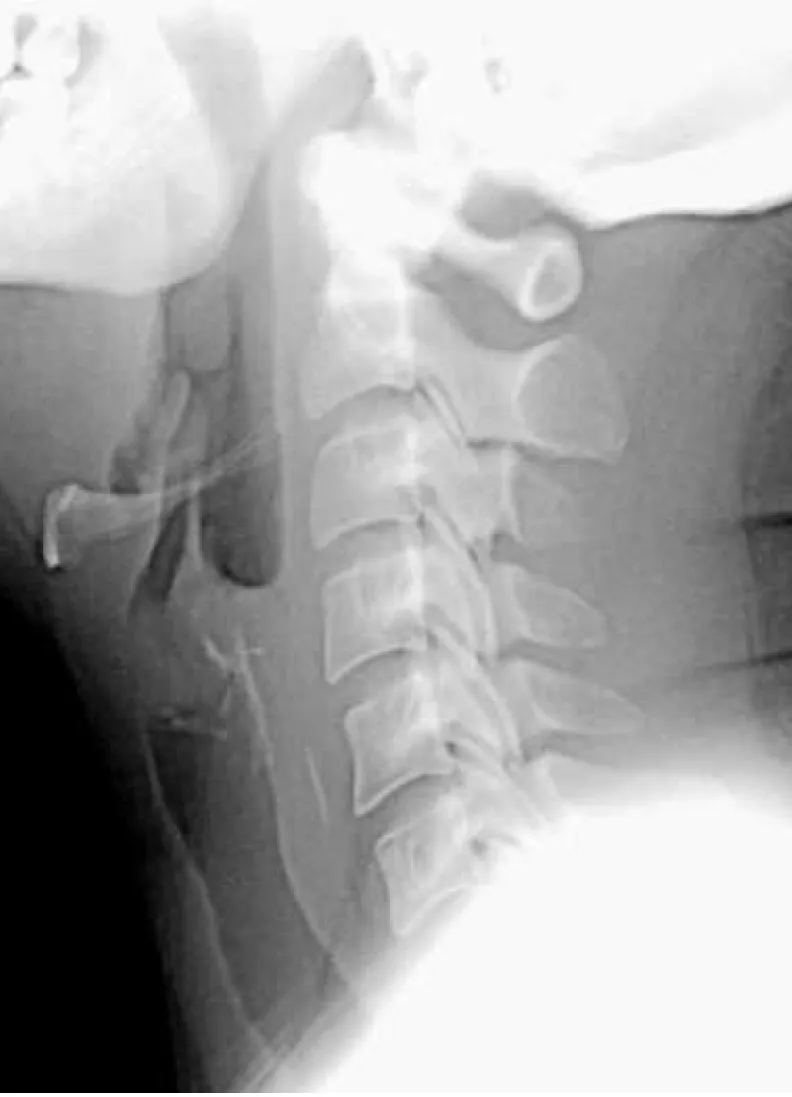

【109-1 醫學(六) 第25題】一中年男性晚飯後出現喉痛、吞嚥困難等症狀就診,頸部X光如下圖,下列敘述何者正確?